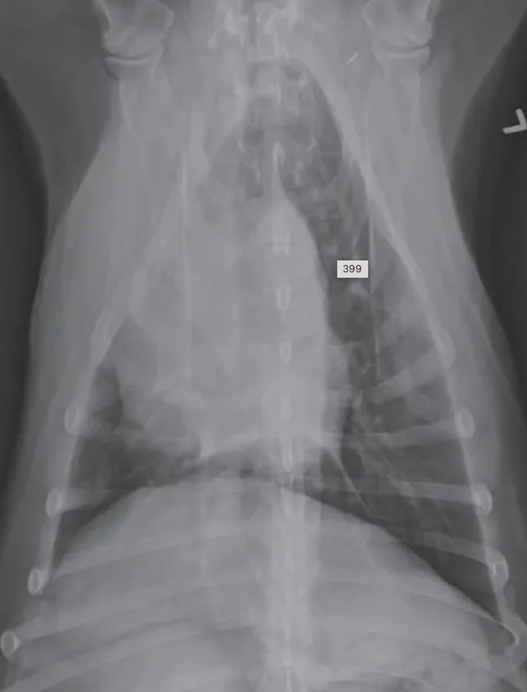

![]() | Mediastinum - abnormal shift - 여기서는 심장이 오른쪽으로 붙음 - 무기폐, 폐자름술, 폐종양일 때 발생 |

![]() | - 옆으로 몇 분 누워있었더니 무기폐 생긴 환자. - 무기폐가 생겨 심장이 왼쪽/오른쪽으로 틀어질 수 있음. - 섣불리 좌심비대로 평가하면 X |